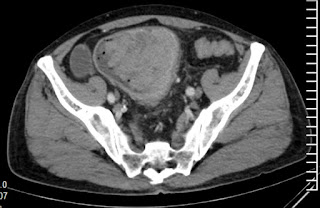

Endoscopic biopsy suggested well differentiated adenocarcinoma. Contrast enhanced abdominal computed tomography scan showed large, non obstructing tumor involving distal sigmoid colon (Figure 1).

Figure 1: Contrast enhanced abdominal computed tomography scan showing large enhancing tumor in distal sigmoid colon